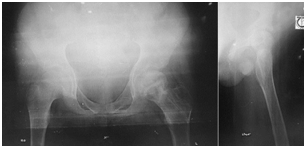

Excellent union was achieved within 3 months (Figure 2-5).

Figure 4 After 2½ months union achieved.

Figure 5 After removal of Ilizarov fixation, good union is achieved.